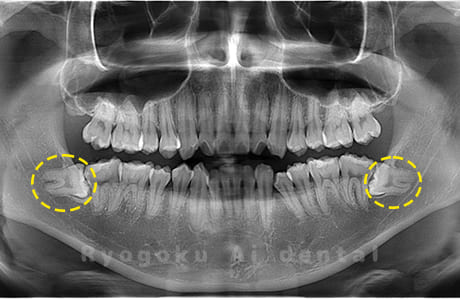

斜めに生えている親知らず

親知らずが斜めに生えて隣の歯にぶつかって圧迫してしまうタイプです。

このタイプが最も多いです。このタイプは虫歯になりやすいだけでなく、隣の歯を圧迫し、咬み合わせや歯並びに影響が出る場合もあるので抜歯をおすすめします。